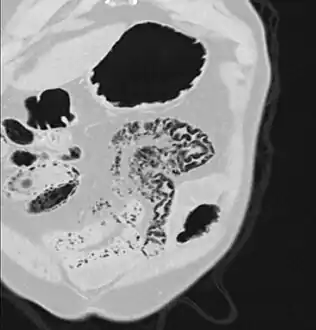

- Pneumatosis intestinalis in computed tomography with intestinal ischemia. Lung window for better representation of the gas deposits in the intestinal walls.